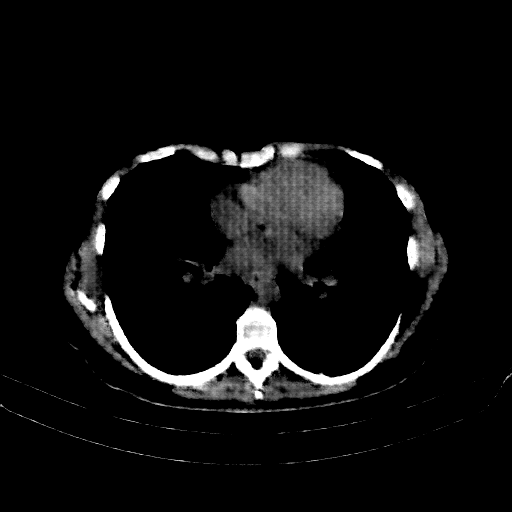

Image Grid

4Γ—3 grid: Rows show different image types (Original NATIVE, Reconstructed NATIVE, Original VENOUS, Generated VENOUS), Columns show windowing techniques (No Window, Lung Window, Mediastinum Window)

Reconstructed NATIVE CT scan (cycle consistency)

Full window (WL 1023.5, WW 4095 β†’ Low βˆ’1024, High +3071)

Lung window (WL -600, WW 1500 β†’ Low βˆ’1350, High +150)

Mediastinum window (WL 40, WW 400 β†’ Low βˆ’160, High +240)